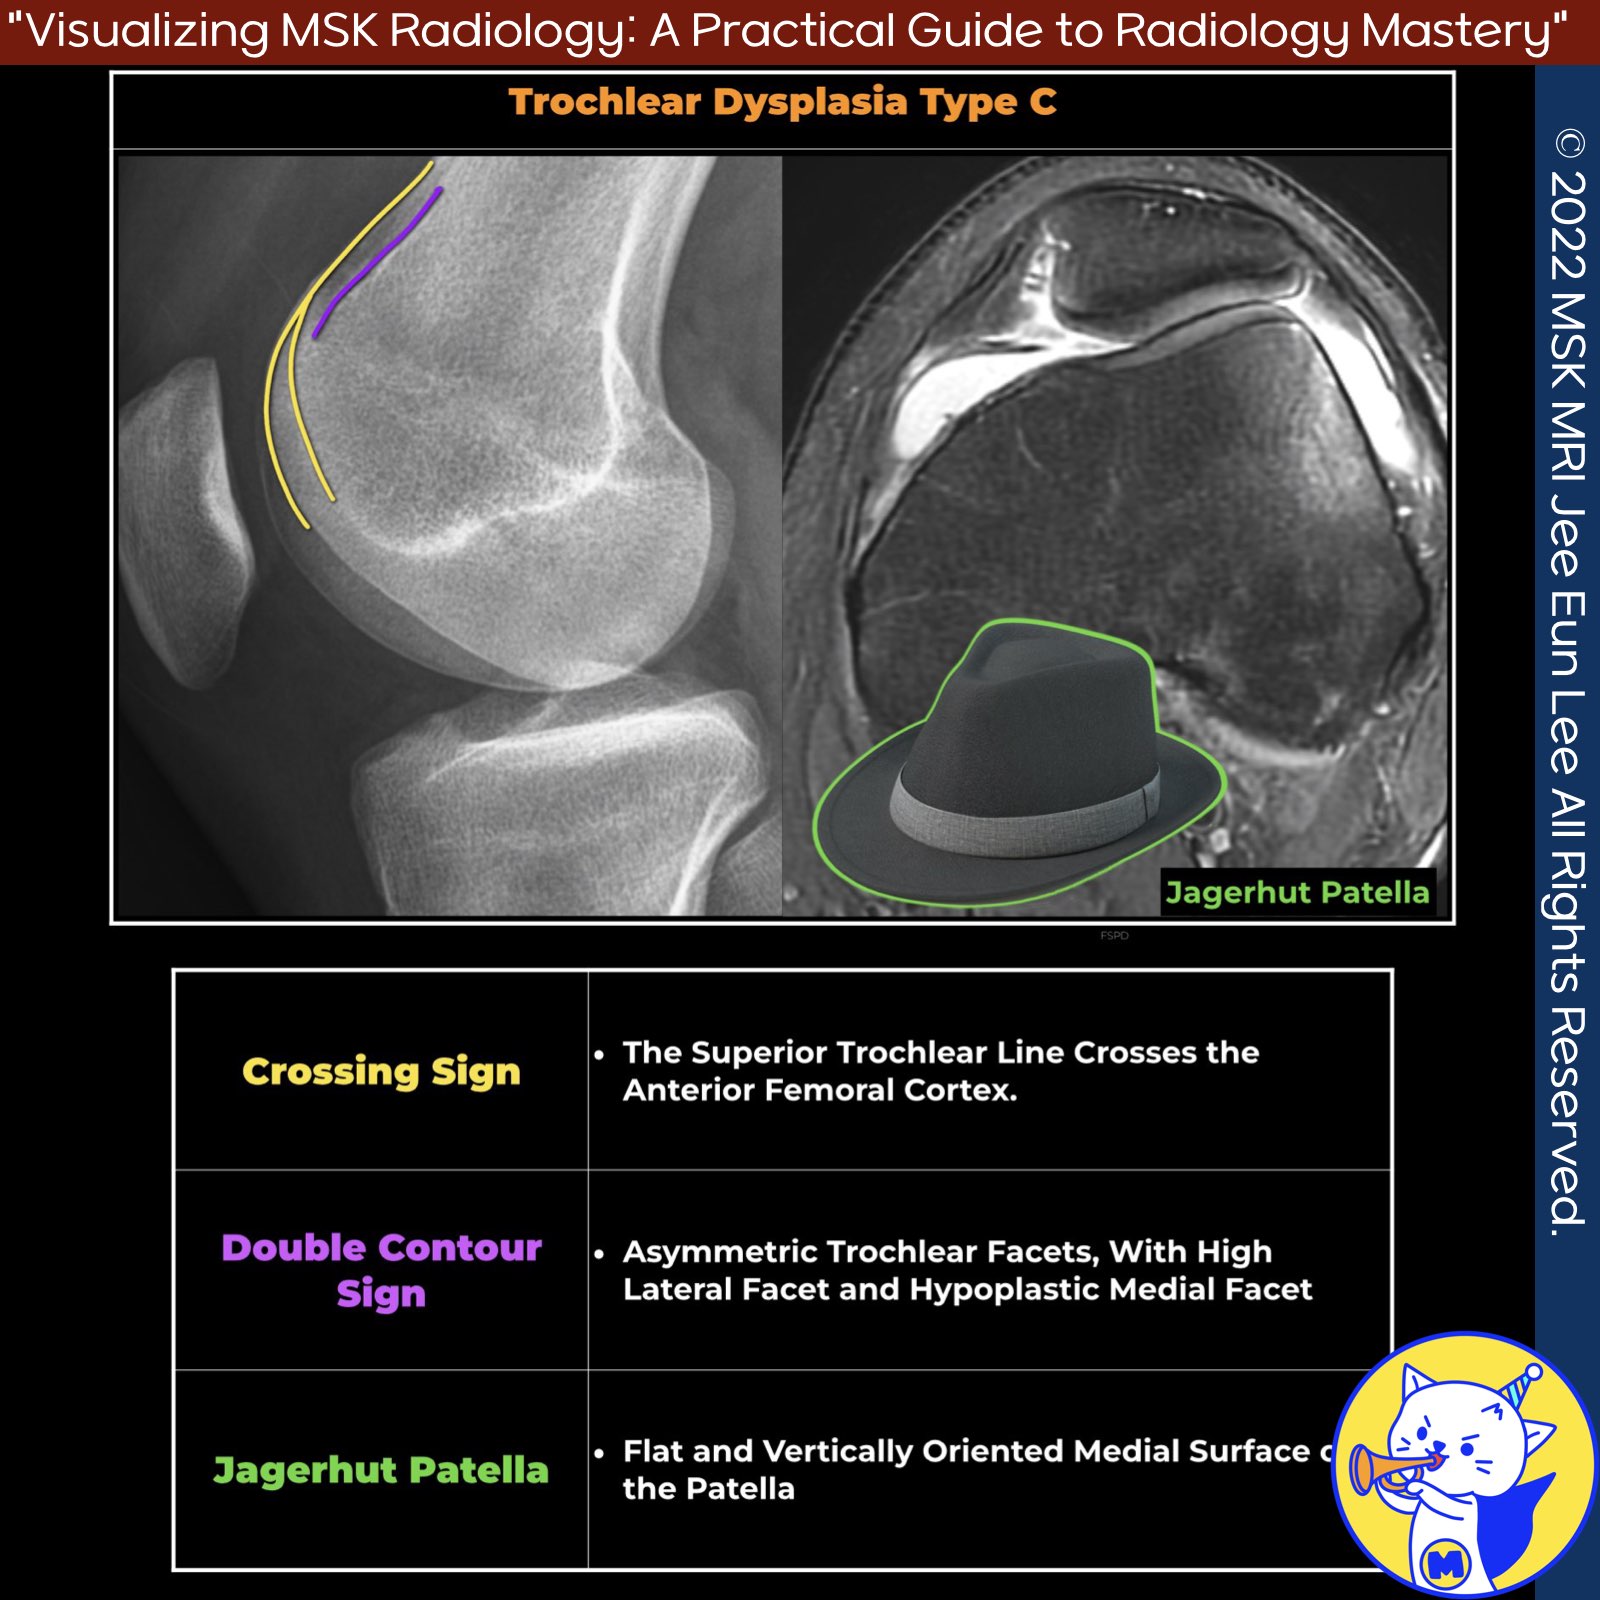

📌 Dejour et al. Classification of Trochlear Dysplasia

3️⃣ Type C

- Signs: Crossing sign and double contour sign laterally

- Axial View: Asymmetry of femoral condyles with hypoplastic medial condyle

- Description: The crossing sign and the double contour sign are present, but there is no spur. On axial views, the medial facet is hypoplastic.